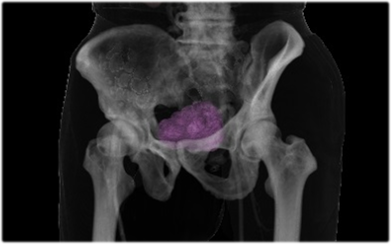

20220914082754.jpg。放射線科|八潮中央総合病院。正常画像と並べてわかる腹部・骨盤部MRI―ここが読影のポイント。対象検査部位・撮像手法|UNB住吉神社前クリニック 放射線科。「腹部のMRI」荒木 力定価: ¥ 13000#荒木力 #荒木_力 #本